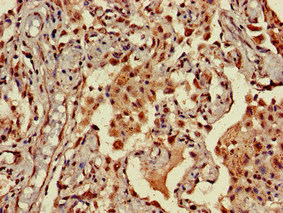

Immunohistochemistry of paraffin-embedded human liver tissue using CSB-PA856441LA01HU at dilution of 1:100